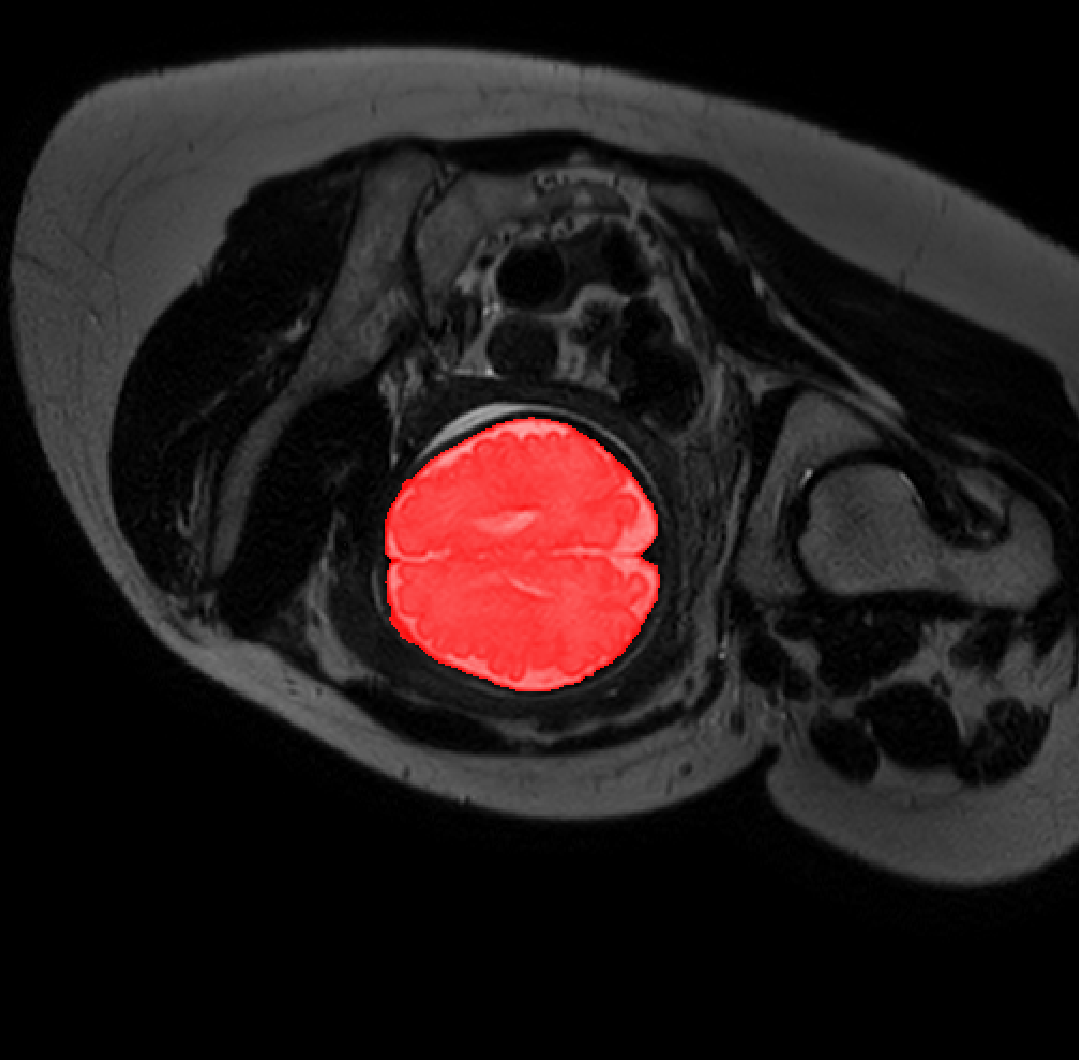

Table 1 lists average of quantitative evaluation results of these experiments and Figure 2 shows results obtained from each image. Figure 3 shows examples of the obtained segmentations.

Figure 3: Example of ICV segmentations in images acquired in axial (left), coronal (middle) and sagittal (right) planes. Top row: A slice from T2-weigted image; Second row: Automatic segmentations obtained using 7 training images from the representative imaging planes; Third row: Automatic segmentations obtained using all 21 training images from all 3 image orientations; Bottom row: Manual segmentation.